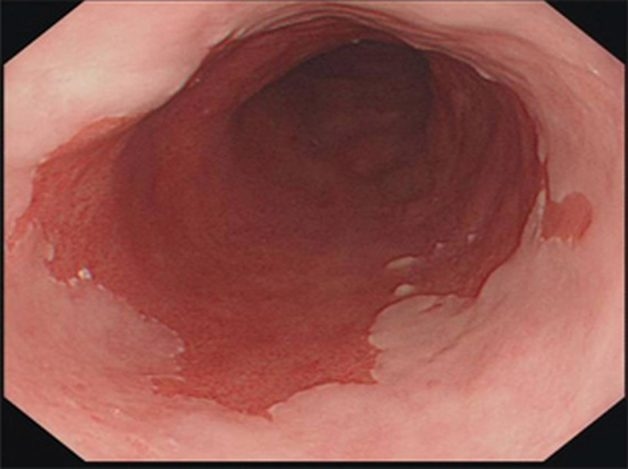

Hình ảnh nội soi barrett thực quản

– Barrett thực quản